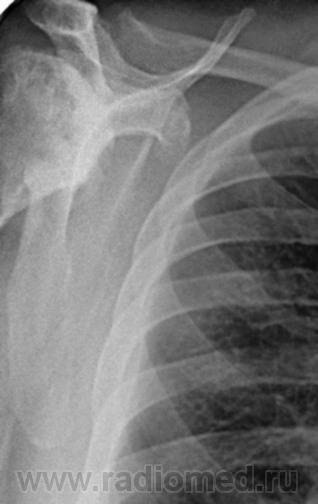

Пациент 60 лет, при прохождении проверочной флюорографии  обнаружены изменения со сторны плечевых суставов.Водитель троллейбуса.Страдает избыточной массой тела, люмбальгией, артороз коленных суставов.Непосредственно жалобы на плечевые суставы в медицинских документах не отражены. Какое будет мнение у коллег?

Пациент жалоб со сторны плечевых суставов не предъяляет и не помнит что бы когда- то что то беспокоило.Данных за сирингомиелию нет.

Александр, конечно надо доснять плечевые суставы... Из того, что есть: видимые отделы плечевых костей выглядят довольно симметрично, хотя слева и похуже, думаю - артроз. Весьма настораживает левая лопатка на предмет хондросаркомы

Снимки плечевых суставов.

Уважаемый Александр, приходиться признать, что на цифровой рентгенограмме легких изменения плечевых суставов видны лучше, чем на "обрезаных" и недоэкспонированых снимках суставов. По имеющимся данным могу только сказать, что деф. артроз с кистовидной перестройкой структуры есть. Под хрящевой опухолью (возможно - хондросаркома) левой лопатки я имела в виду тень, отмеченую красными стрелками, которая в поле снимка не вошла. Моя вина - в силу специфики работы такие узкоформатные снимки давно были вредными, т.к. очень часто патология остается за пределами снимка. Остается рекомендовать рентгенография левой лопатки в прямой передне-задней и косой проекциях, а лучше - КТ...